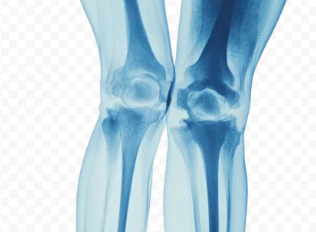

4. 오금 통증 진단 방법

✔ X-ray 검사 – 뼈 & 관절 상태 확인(관절염, 연골 손상 진단 가능)

✔ 초음파 검사 – 베이커 낭종 여부 확인

✔ MRI 검사 – 인대 손상, 반월상연골판 손상 확인

✔ 혈액 검사 – 혈전 여부 확인(심부정맥 혈전증 감별)

📌 즉, 오금 통증 원인을 정확히 파악하기 위해 X-ray, MRI, 초음파, 혈액 검사가 필요할 수 있다.